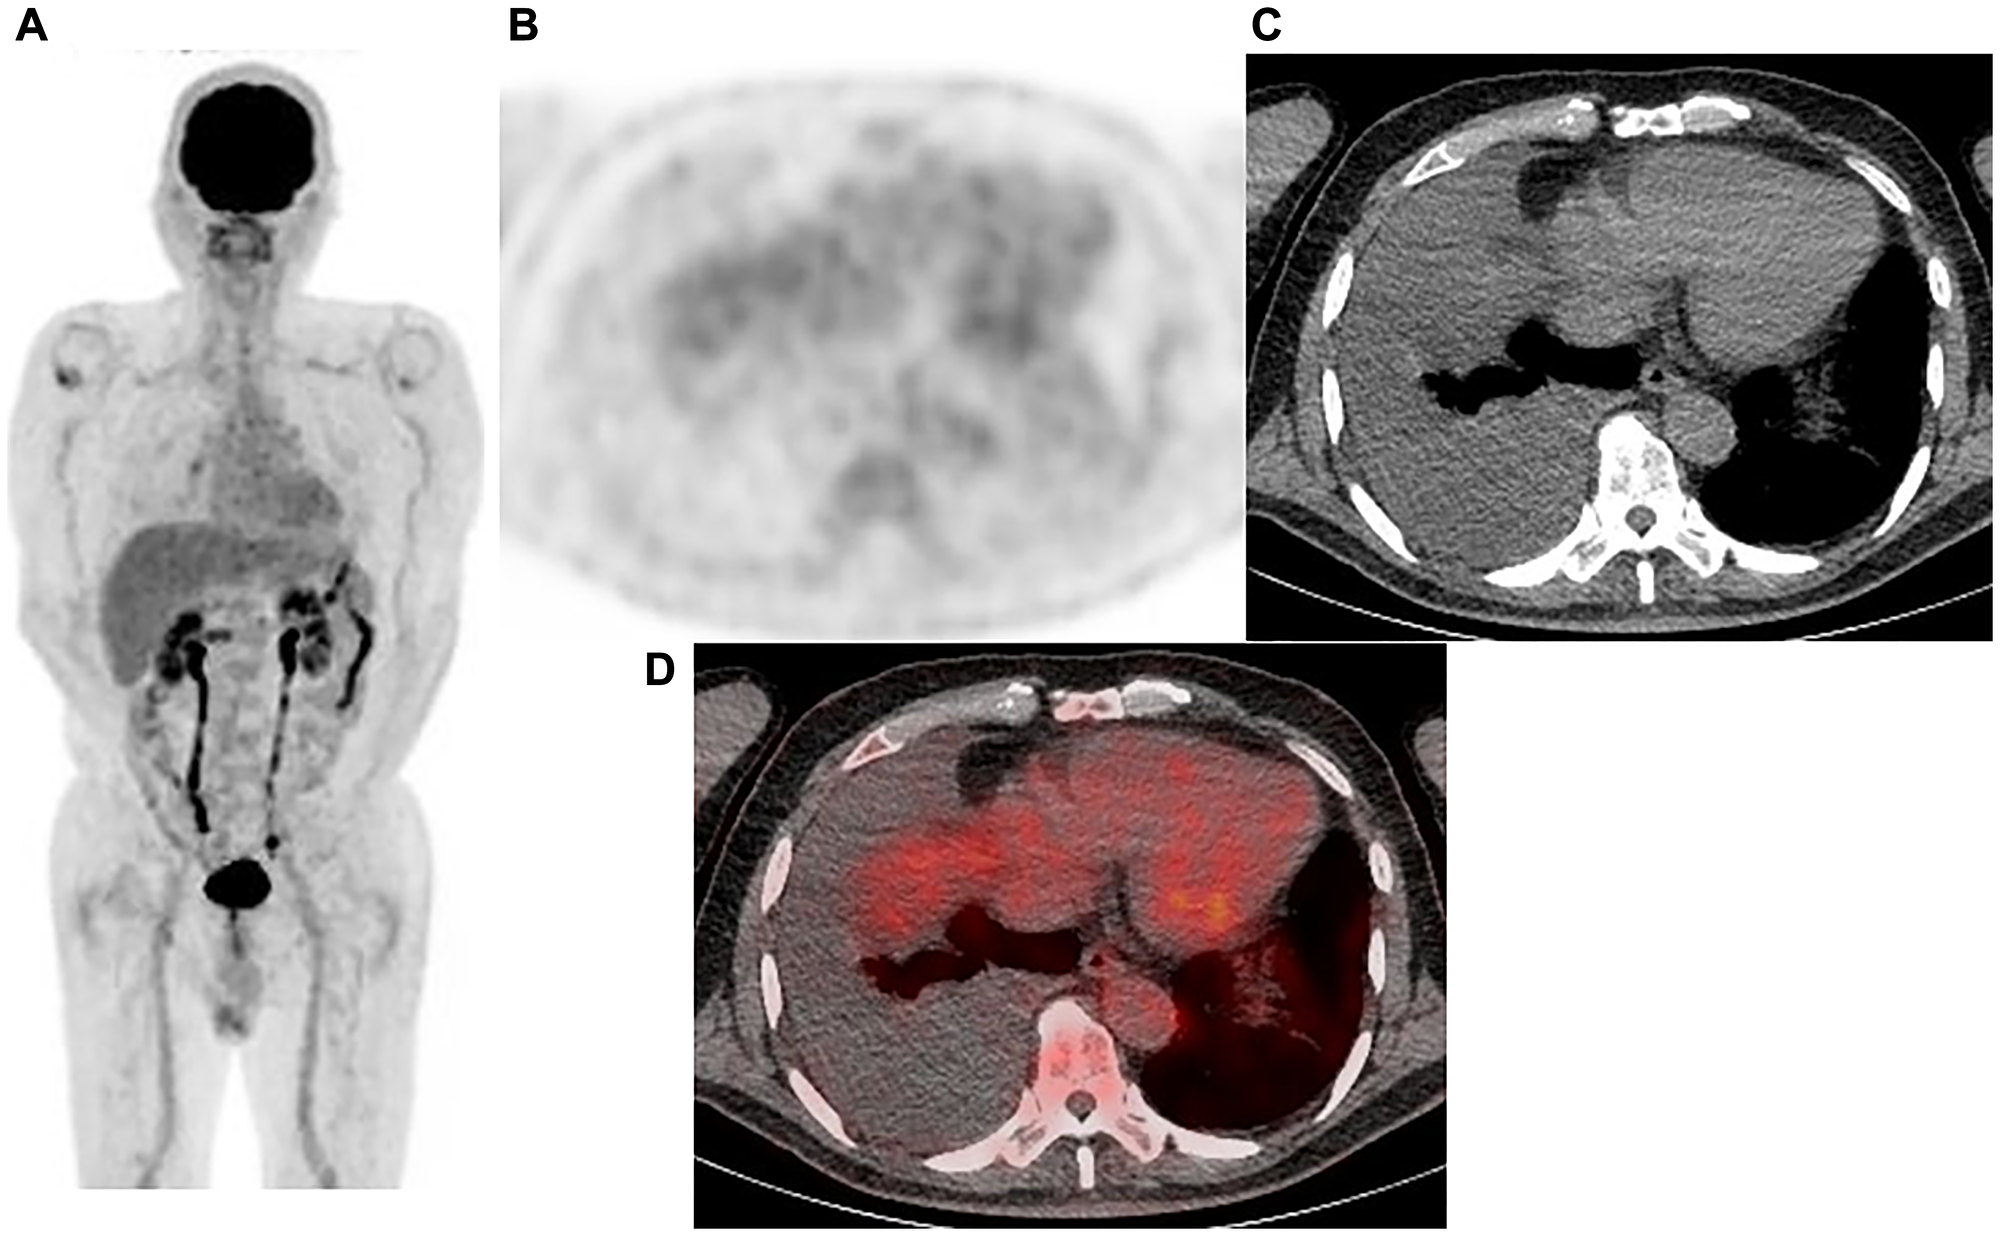

Representative case: 77-year-old male with right malignant pleural mesothelioma (epithelial type)

Figure 2: Representative case: 77-year-old male with right malignant pleural mesothelioma (epithelial type). (A) Maximum intensity projection (MIP) from FDG-PET, (B) Axial FDG-PET, (C) axial CT, and (D) fused FDG-PET/CT. Pleural effusion in the right pleural cavity was noted, while no FDG uptake was observed. The diagnosis was negative with protocol A (output value 0.127), B (grade 2), and C, whereas it was positive with protocol D (output value 0.448). VATS showed the sample to be positive, a malignant pleural mesothelioma (epithelial type).